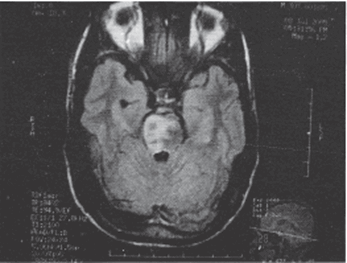

Основополагающим методом диагностики болезни Галлервордена-Шпатца выступает МРТ. Во всех типичных вариантах патологии в режиме Т2 на МРТ головного мозга определяется расположенная в области бледного шара гиперинтенсивная зона овальной формы, окруженная еще большей гипоинтенсивной зоной. Подобная МРТ-картина является патогномоничной и получила название «глаз тигра». Гипоинтенсивная зона представляет собой «глаз», а гиперинтенсивная — его «зрачок». Время появления этого признака на томограммах пока дискутируется. По мнению одних авторов «глаз тигра» может появляться еще до клинической манифестации болезни, по мнению других — через несколько лет от дебюта клинических симптомов.

Рисунок 1. T2 Flair МРТ снимок, демонстрирующий билатеральный инфаркт моста (затронувший правую сторону больше, чем левую) (Paliwal et al., 2007)